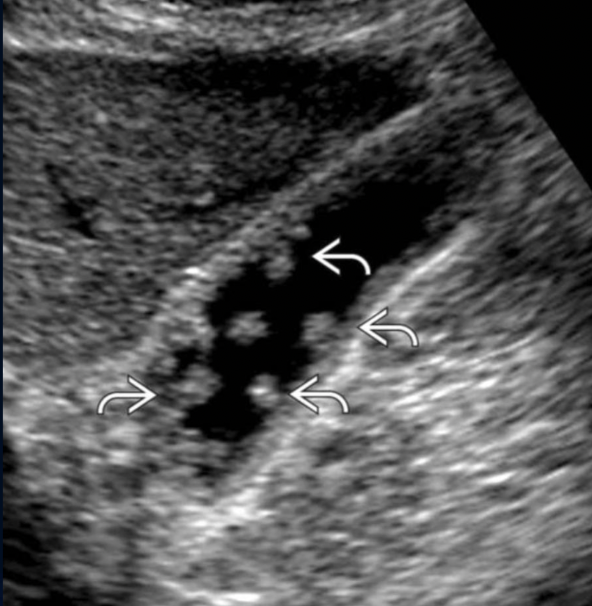

Path?

Case 1: Calculus presen with acoustic shadowing

Case 2: Common Bile Duct is Dilated + Echogenic Material Present within

Both Choledocholithiasis